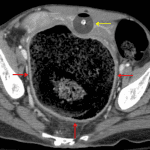

- Massive rectal distension measuring up to 11 cm in diameter with a large volume of formed stool in the rectum

- Distal sigmoid colon and rectal wall thickening and surrounding fat stranding

- Diffuse colonic distension with a moderate colonic stool burden

- Circumferential mural thickening of the urinary bladder and urothelial thickening and enhancement of both ureters

- Bladder is decompressed around a Foley catheter and is ventrally displaced and flattened by the massively distended rectum

- Stercoral proctocolitis

Massive distension of the rectum and sigmoid colon with findings concerning for fecal impaction and stercoral proctocolitis. No evidence of perforation, abscess, or ischemia.